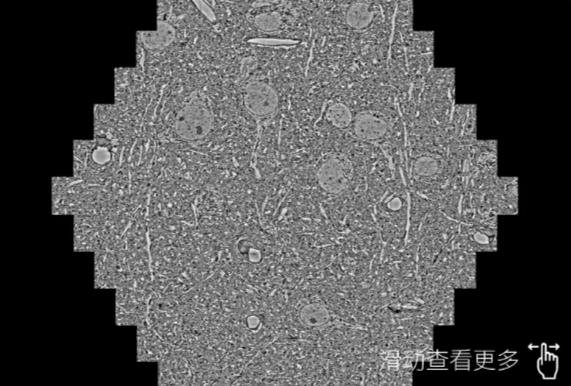

鼠脑切片。左图使用石柱蔡司石柱扫描电镜MultiSEM706对165μmx143pm面积区域成像,耗时仅需1.5秒。右图为鼠脑切片中30μm区域放大效果。样品由芝加哥大学B.Kasthuri提供。

使用蔡司高速石柱扫描电镜MultiSEM对1mm²人脑皮层组织进行高分辨成像,并对其中的各种细胞结构进行三维重构分析。左图展示了2x3mm²组织平面中锥体神经元的三维重构效果。右图显示了局部体积神经元三维重构。图像由哈佛大学chtman实验室提供,渲染图由D. Berger 制作。